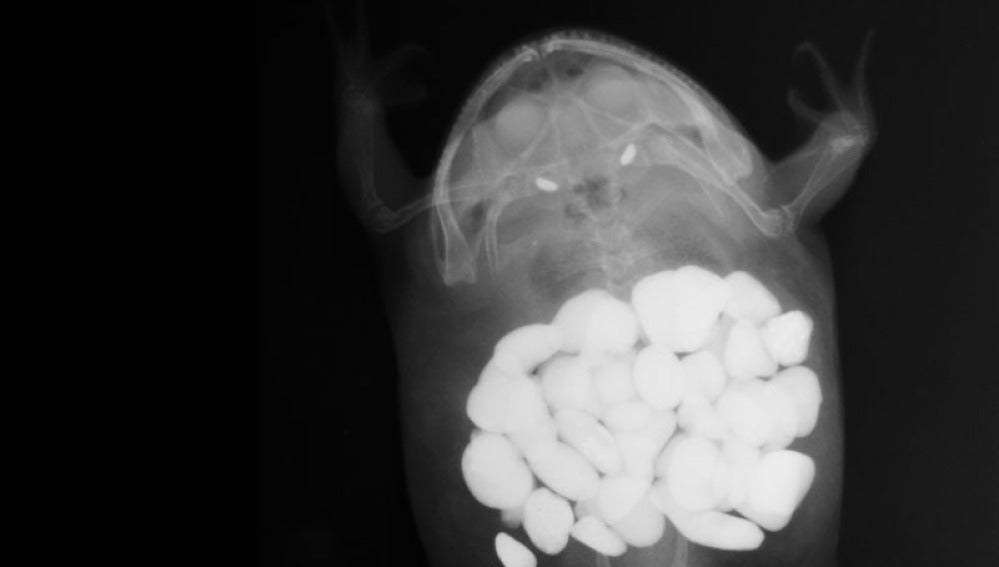

El estómago de una rana con unas 30 piedras de decoración | veterinarypracticenews.com Esta radiografía muestra 43 calcetines estómago de un Gran Danés | veterinarypracticenews.com Una navaja en un perro labrador | veterinarypracticenews.com Un extraterrestre de juguete en el cuerpo de un gato | veterinarypracticenews.com Una bombilla encontrada en un perro golden retriever | veterinarypracticenews.com El cuerpo de una rana con un plátano de juguete en su interior | veterinarypracticenews.com Un brocheta de cocina en el cuerpo de un perro | veterinarypracticenews.com Más sobre este tema: perros gatos